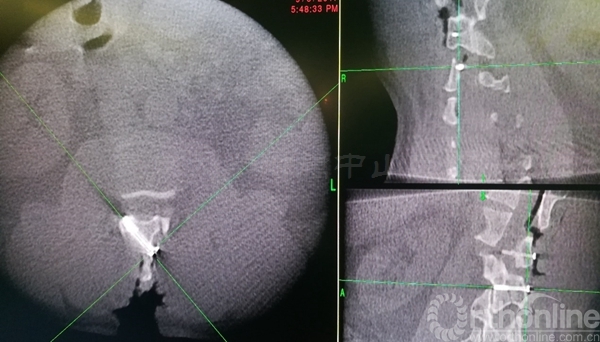

术中椎板截骨行肿瘤切除后,椎板回植术,回植椎板采用空心螺钉固定

术后肌力恢复至4+级,无脑脊液漏,X线片及CT平扫显示椎板回植位置满意,空心钉固定牢靠。术后病理诊断为脊膜瘤伴细胞丰富

术后三个月患者腰背痛完全缓解,肌力已恢复至5级,下肢麻木感消失。CT显示:椎板截骨面已骨性愈合,无移位,椎管容积与术前无明显差异